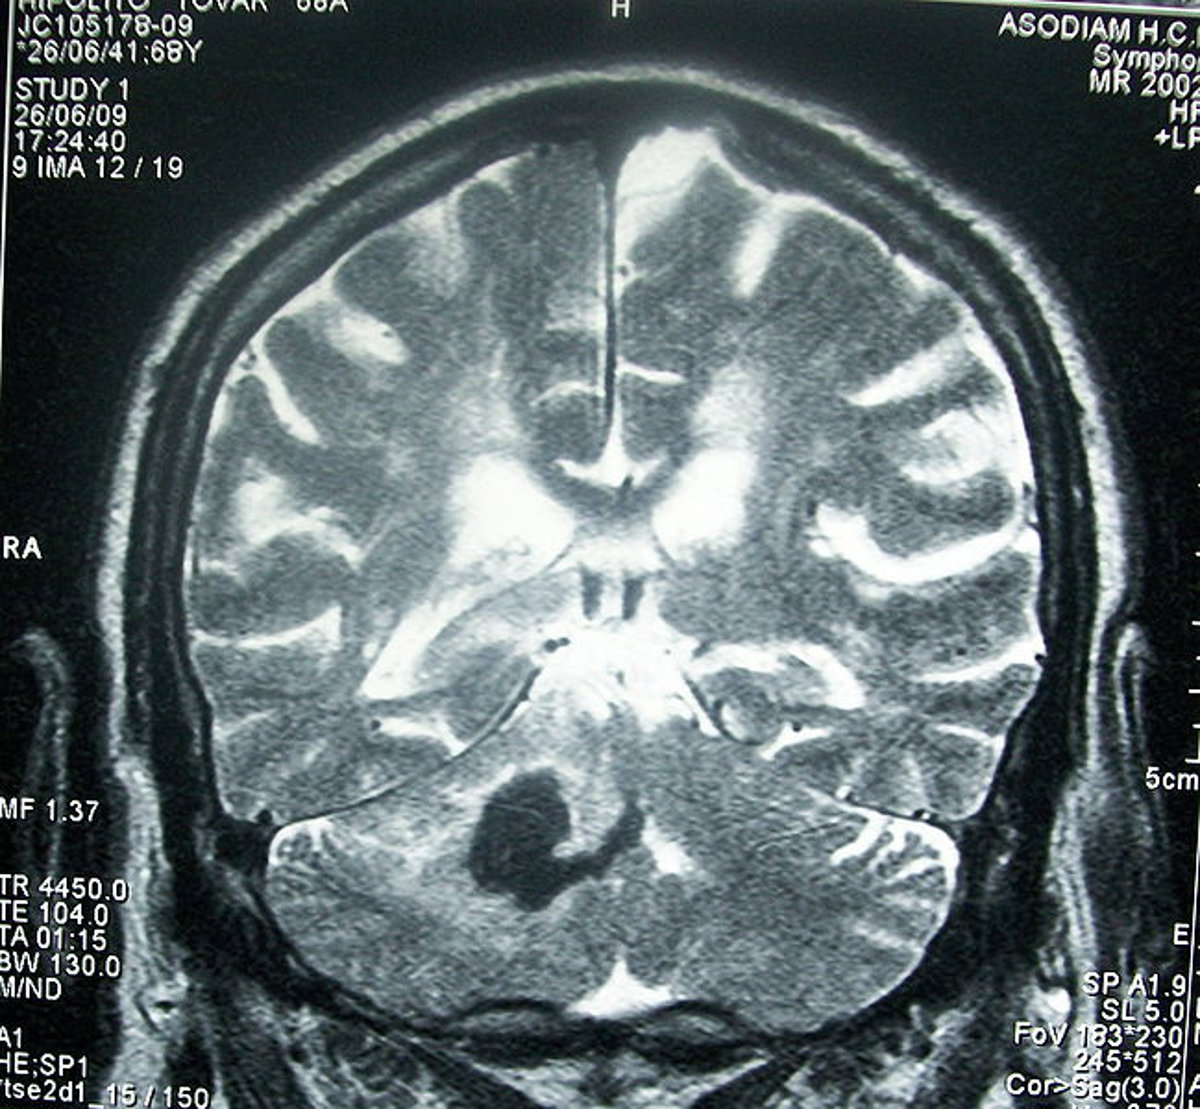

Cerebro

BOBJGALINDO/WIKIMEDIA COMMONS